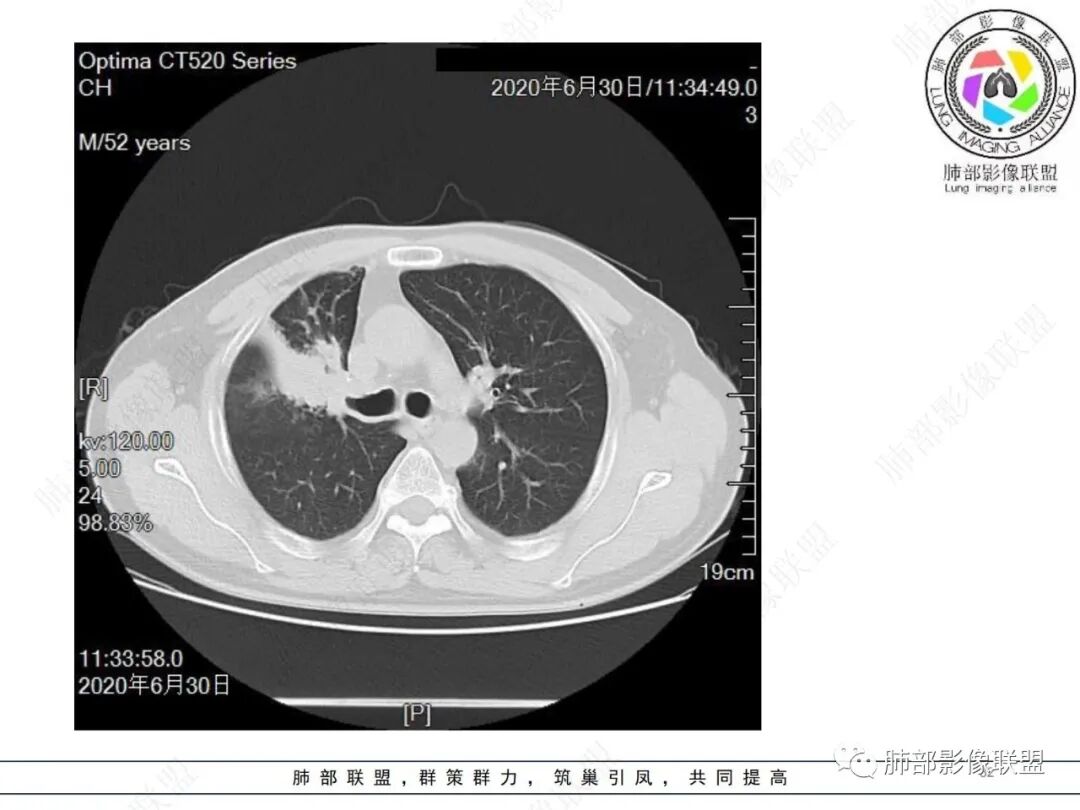

中年男性,有长期吸烟史,右肺上叶不规则肿块,边缘膨隆有分叶,支气管截断,不均匀强化,内有多灶性坏死,癌胚抗原升高,考虑肺癌可能性大,鳞癌可能。鉴别腺癌。

右肺上叶不规则形软组织密度肿块影,边缘见分叶,毛刺,病灶呈宽基底与胸膜相连,病灶内见坏死,增强扫描呈不均匀性强化,右肺上叶支气管截断,纵隔内见肿大淋巴结,肿瘤标志物增高,考虑鳞癌可能,鉴别小细胞癌,腺癌。

右肺上叶不规则肿块,分叶、毛刺,上叶支气管截断,断端圆钝,不均匀强化,其内空泡及坏死,坏死边界不清,考虑腺癌或腺鳞癌,鉴别鳞癌

中年男性,长期吸烟,CT示右肺上叶肿块影,有分叶,毛刺,胸膜牵拉,支气管截断,边缘斑片影,病变内有坏死,强化,淋巴结肿大,首先考虑鳞癌可能性大,鉴别腺鳞癌

右肺上叶占位,支气管阻塞截断,病变周围可见结节及斑片状影,密度不均,坏死边缘不清,纵隔淋巴结肿大,中年男子,吸烟史,考虑鳞癌、腺鳞癌,鉴别结核

除了年龄,吸烟,湖泊样坏死符合鳞癌,其他都不符合,支气管截断,不在肿块中央,远处也没有明显阻塞样改变,更像爬行后截断,肿瘤标志物CEA高得厉害,其他鳞癌标志物并不高。这种坏死,低分化腺癌一样常见,强化远端也有强化,不符合鳞癌,所以我考虑低分化腺癌(伴或不伴有神经内分泌分化)或者肉瘤样癌。

边缘都是强化的肿瘤组织,鳞癌是不会这样的,符合腺癌

不符合鳞癌有四点:1,截断的支气管不在肿块中央,而是外朝内爬行(肿块外缘大于近端)2、支气管截断在前段,前段远端没有阻塞性改变。3、鳞癌是近端强化,远端为阻塞性的不强化粘液栓或明显强化的不张肺组织,这个是中间坏死,周围强化的肿瘤组织。4、肿瘤标志物CEA增高太明显,鳞癌标志物不高。